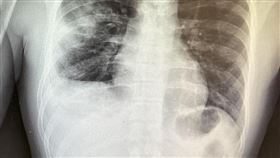

30多歲年輕人染流感 「肺塌陷」險沒呼吸

疫情後許多人都漸漸不戴口罩,不過近來流感疫情嚴重,加...